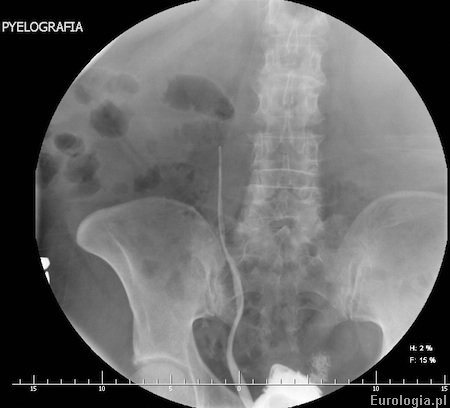

Fot. Ureteropielografia wstępująca u pacjenta z wodonerczem prawostronnym w przebiegu nowotworu urothelialnego moczowodu - widoczny brak przechodzenia kontrastu poza przeszkodę w moczowdzie